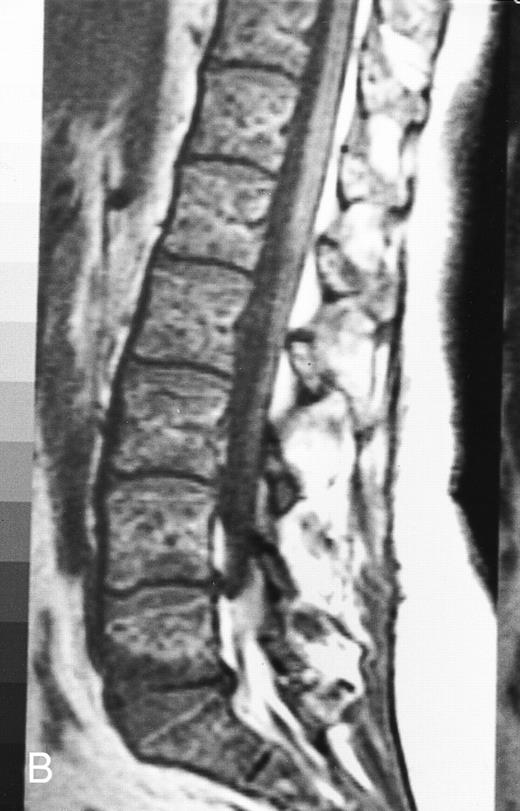

Normal bone marrow in an 8-year-old child. Coronal T1-weighted (TR/TE, 600/11) MR image of the abdomen and pelvis shows persistent red marrow in the spine (arrows). Note bright signal of fatty marrow in the femoral epiphyses and apophyses (long arrows).